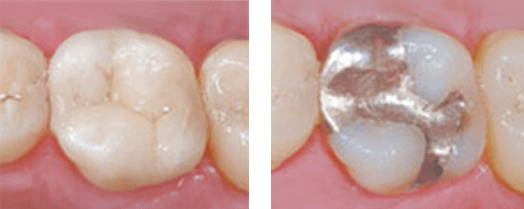

There are two main types of dental fillings: metal and metal-free. Metal fillings can be either made of amalgam, which is a silver-colored option used for over 100 years, or cast gold. Amalgam contains mercury, silver, tin, and copper. Cast gold is a combination of gold and other metals, but does not include mercury.

Metal-free fillings are either composite or porcelain. Composite is a mix of glass and plastic that bond to the rest of the tooth for a natural look. Porcelain is a high-tech ceramic that is not only natural looking, but it is also more difficult to stain than the composite option.